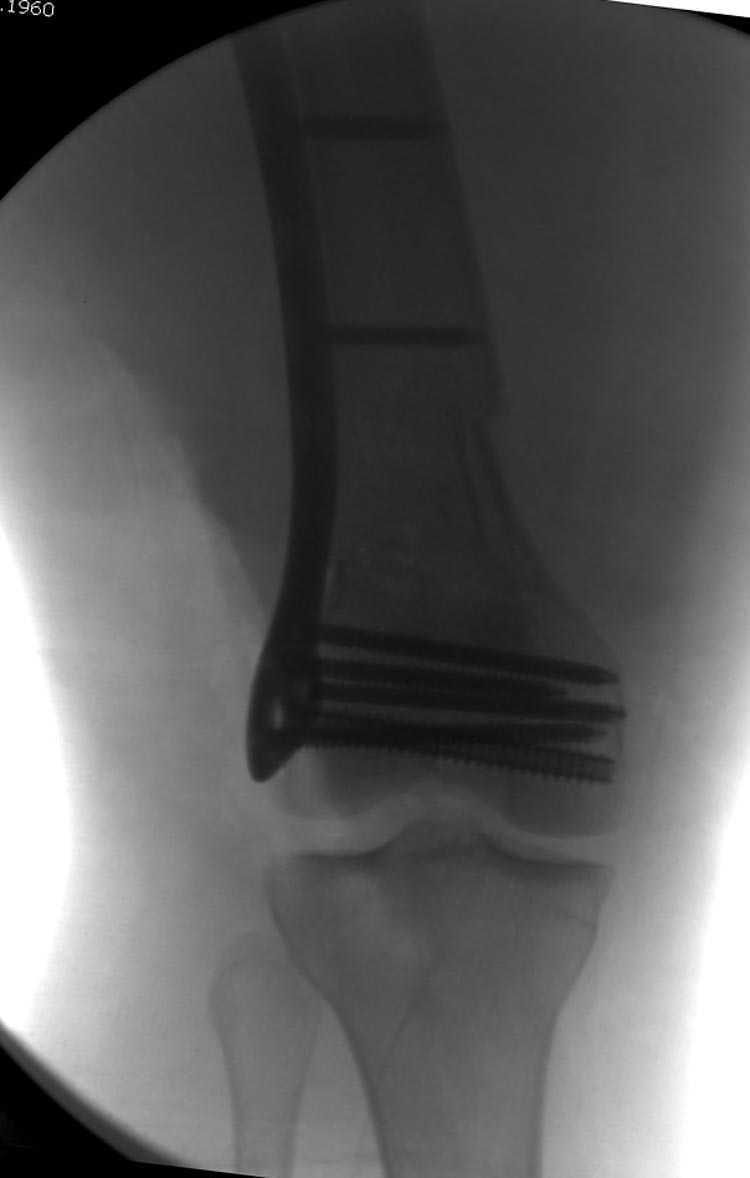

Это перелом не нижней трети, а дистального суставного конца, с распространением на диафиз. Что-то между C2 и C3. Но пока ближе к C2 по увиденному - вторую проекцию еще не показали.

На профиле стало видно, что открываться придется, это перелом C3, хотя можно назвать и C2+, т.е. с еще и фронтальным раскалыванием одного мыщелка. Надо сделать медиальную артротомию, ступеньку на внутреннем мыщелке устранить, ввести либо несколько временных спиц спереди назад, или сразу винт вдоль эллипса мыщелка. А дальше как выше написано - дистрактор, и штифтовать. Учитывая наличие открытого колена - вполне уместно ретроградно.